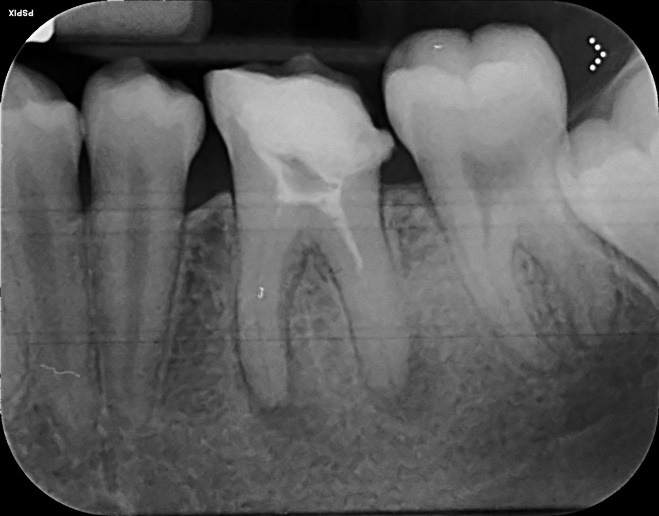

Lower Molar and premolar Primary root canal treatment